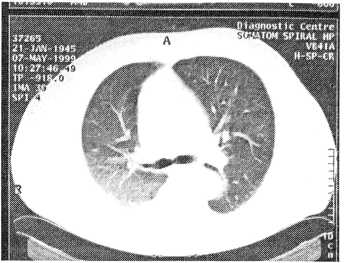

Рис. 1. Компьютерная томограмма больного В. при поступлении